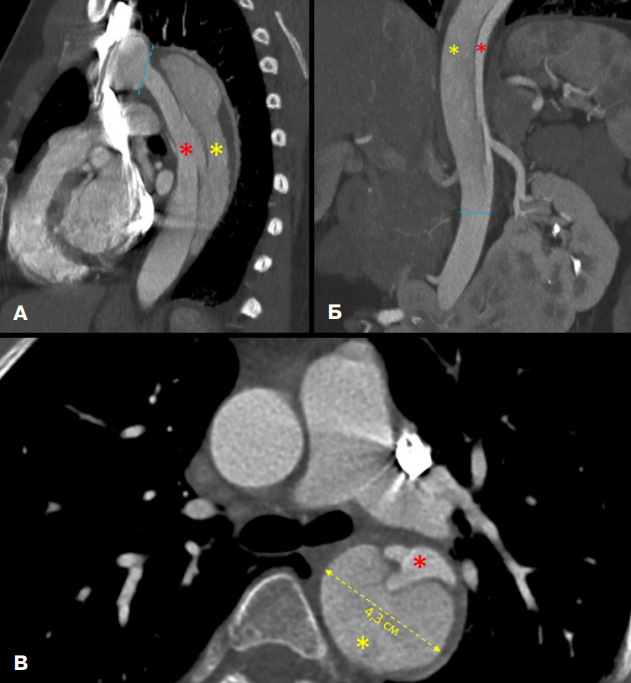

По решению врачебного консилиума для верификации диагноза выполнены КТ-панаортография и эхокардиография. Данные КТ-панаортографии подтвердили наличие расслоения, протянувшегося от уровня, расположенного дистальнее отхождения левой подключичной артерии, и до инфраренального сегмента брюшной аорты. Сопутствующей находкой явилась подковообразная почка с очагом инфаркта в паренхиме правой половины почки (рис. 1, 2).

Рис. 1. КТ-панаортография пациентки с РА тип III (De Bakey).

Примечание: А — сагиттальная плоскость, Б — фронтальная плоскость, В — аксиальная плоскость. Проксимальная граница расслоения расположена непосредственно после отхождения левой подключичной артерии от дуги аорты, дистальная граница — на уровне инфраренального отдела брюшного отдела аорты (голубые пунктирные линии). Ложный просвет (желтая звезда) имеет больший размер, чем истинный просвет (красная звезда), наибольший диаметр аорты на уровне нисходящей части — 4,3 см. Четко визуализируется только дистальный разрыв интимы в области дистальной границы. Цветное изображение доступно в электронной версии журнала.